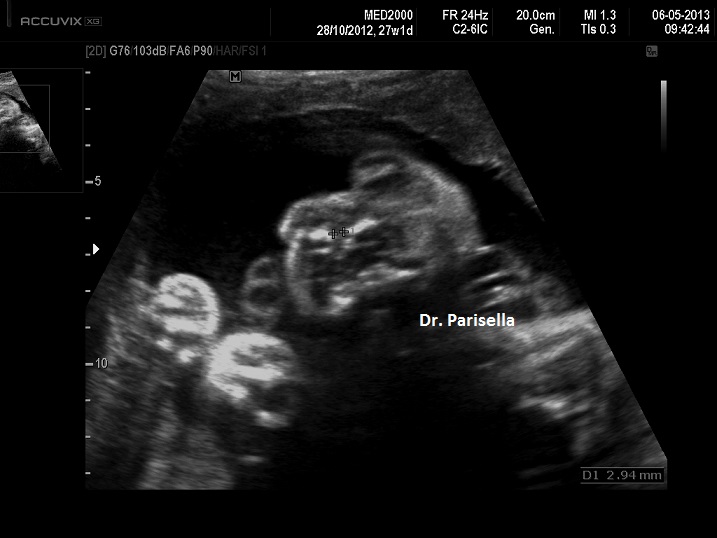

E' una rara collagenopatia a trasmissione autosomica dominante causata da mutazioni del gene COL2A1, che codifica per il collagene tipo 2, caratterizzata da accorciamento rizomelico delle ossa lunghe e ipoplasia mediofacciale (viso tondo e radice del naso piatta); comune è la palatoschisi e occasionalmente l'associazione con la sequenza di Pierre Robin e quindi la presenza di micrognazia. Spesso vi è anche interessamento della colonna vertebrale con platispondilia e schisi coronali.  Segni radiografici sono l'assenza della testa del femore, l'ingrandimento della metafisi prossimale del femore, le epifisi ingrandite.

La diagnosi precoce è impossibile in quanto la biometria delle ossa lunghe diviene anormale solo nel III trimestre di gravidanza.